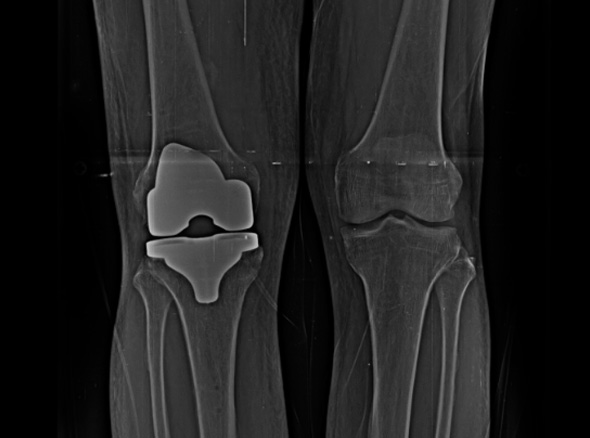

손상된 무릎 뼈를 제거하고, 그 부위에 특수 소재의 금속 재질로 구성된 인공관절을 삽입하는 수술을 시행할 수 있습니다.

관절연골이 망가져 쓸 수 없을 때 관절기능 회복을 위해 시행하며, 인공관절의 수명은 20~30년 정도 됩니다.

인공관절수술은 이러한 환자분들을 대상으로 시행하는 수술로

정밀검진 및 검사를 통해 관절 손상정도를 면밀히 파악하고 꼭 필요한 경우에만 수술을 진행합니다.